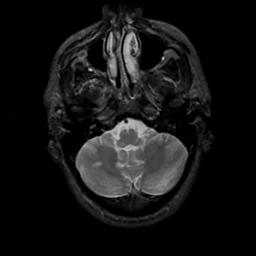

MR Study #6, March 17, 1991 -- Slice #9

[Home][Help][Clinical][Tour 1][Tour 2] Slice 9